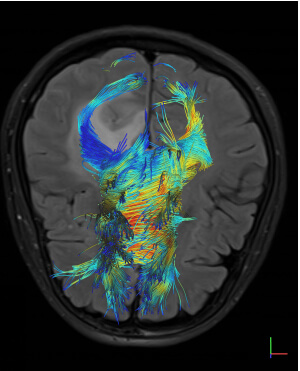

- Special state-of-the-art techniques (fMRI, Multiparametric MRI, Spectroscopy, Tractography, Dynamic Angiography, Neurography, CSF Flow Study)

- Combination of special techniques with high-resolution anatomical images, providing additional information for tissue characterization (number of cells, blood flow and metabolic activity)

- Τractography